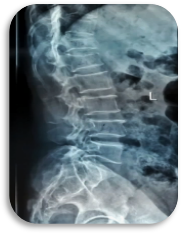

科室设置四个亚专业:创伤骨科以微创开展复杂骨折与多发伤救治,实现骨折愈合与功能恢复同步;手足显微外科凭精细显微操作,开展断指(肢)再植、血管神经损伤修复,游离皮瓣移植创面修复,各类手足畸形矫治;关节与骨质疏松组遵循阶梯化治疗,开展保关节、微创关节置换及各类关节翻修手术,骨质疏松专业实现骨质疏松全生命周期管理,规范抗骨质疏松治疗切实降低骨折风险,改善骨质健康;运动医学专业以关节镜微创技术为核心,诊治各种运动系统损伤,结合康复疗法助力患者重返运动。